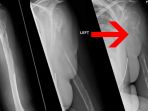

Hasil Scan yang Mengejutkan, Seorang Wanita Didiagnosa Mengidap 'Tulang Hilang'

Wanita berumur 44 tahun yang tak disebutkan namanya ini didiagnosa mengidap penyakit tulang yang hilang.